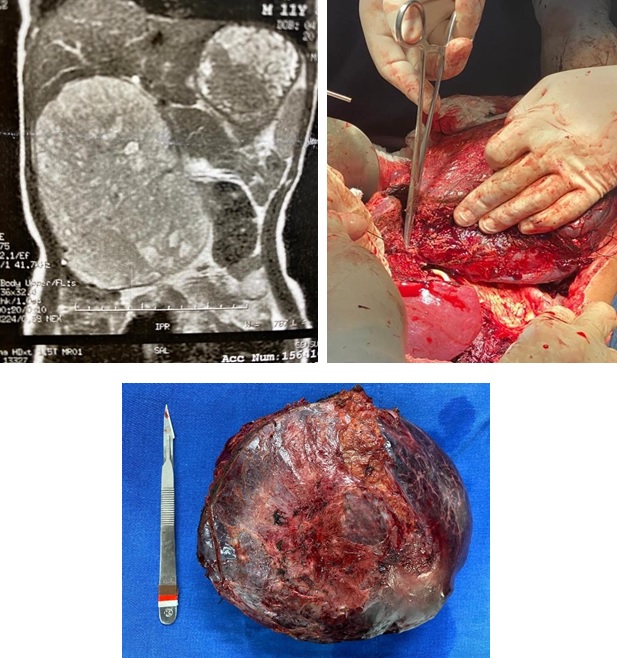

Tumor adrenocortical metastático, uma apresentação atípica: relato de caso

Rodrigo Firmino Schirmbeck Moraes, Emanuela Lando, Julia Pastorello, Cristiane Pagnussat Cechetti, Camila dos Santos do Amaral, Douglas Carvalho Cogo, Giovana Zerwes Vacaro, Marina Ractz Bueno, Nicoli Taiana Henn, Robson Rottenfusser, Alexandre Bueno da Silva, Eduardo Lima Tigre

98-104